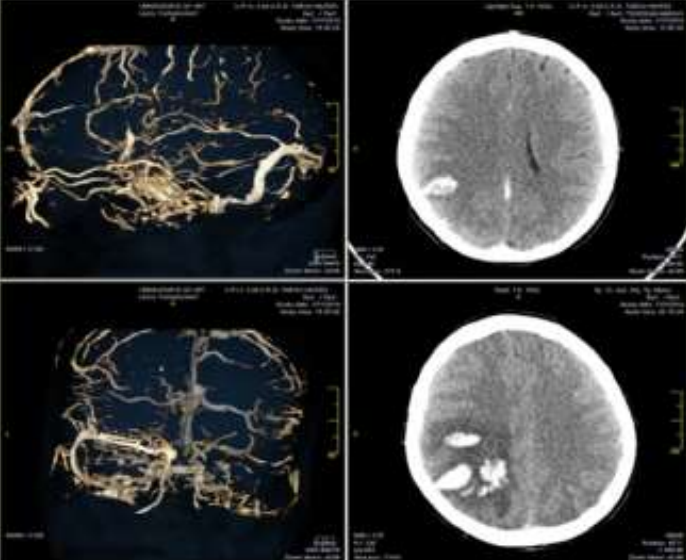

• Ly giải huyết khối hoặc lấy huyết khối

• Phòng ngừa huyết khối tiến triển

• Điều trị tình trạng tăng áp lực nội sọ, co giật và các biến chứng khác

• Với mục tiêu nhằm điều trị tình trạng huyết khối cơ bản, để ngăn ngừa huyết khối tĩnh mạch ở các bộ phận khác của cơ thể, đặc biệt là thuyên tắc phổi và ngăn ngừa sự tái phát của CVT.

Sơ đồ chẩn đoán và điều trị CVT theo Hội đột quỵ Hoa Kỳ 2011

Đối với hầu hết người bệnh CVT chống đông máu bằng LMWH tiêm dưới da hoặc heparin tiêm tĩnh mạch cho người bệnh trưởng thành không có chống chỉ định. Nhồi máu não hoặc chảy máu não, hoặc chảy máu dưới nhện do CVT không phải là chống chỉ định điều trị chống đông máu. Ưu tiên dùng LMWH trừ khi người bệnh có khả năng phải can thiệp xâm lấn như phẫu thuật, hoặc có chống chỉ định với LMWH như suy thận.

Thường khởi đầu bằng heparin trọng lượng phân tử thấp (LMWH) hoặc heparin không phân đoạn(UFH) trong giai đoạn cấp tính. Kháng vitamin K đường uống dùng sau giai đoạn cấp tính, khi đạt đến INR 2-3 thì ngừng heparin trọng lượng phân tử thấp (LMWH) hoặc heparin không phân đoạn.